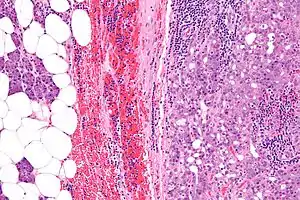

| Micrograph of an acinic cell carcinoma (right of image) and acinar glands (parotid gland - left of image). H&E stain. | |

Basophilic, bland cells similar to acinar cells. Growth pattern: solid - acinar cells, microcytic - small cystic spaces mucinous or eosinophilic, papillary-cystic - large cystic lined by epithelium, follicular - similar to thyroid tissue.

Intermed. mag.